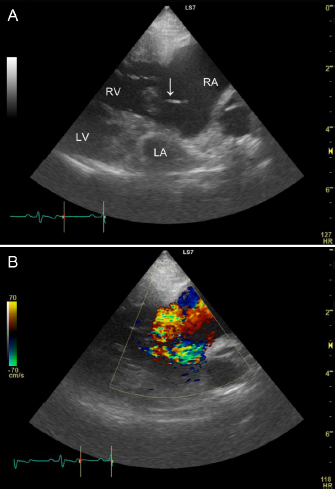

The patient re-presented with abdominal enlargement and dyspnea 405 days after the initial hospitalization. The owner reported that the abdominal enlargement appeared to have gotten worse in recent days and that respiratory distress had been observed since the previous night. The owner said he was unable to give the patient two doses of medicine because of dyspnea. Vital signs included a heart rate of 120 bpm, respiratory rate of 48 breaths/minute, blood pressure of 81/56 mmHg, and rectal temperature of 35.8°C. Peripheral oxygen saturation was 91%, and the patient had lost weight (to 6.98 kg). A grade 3/6 heart murmur was detected at the right cardiac apex. A SNAP Heartworm RT test (IDEXX) was negative in March of that year, and the patient had been prescribed oral moxidectin (MOXIHEART CHEWABLE; Virbac Japan, Osaka, Japan) every month. Laboratory testing revealed a low packed cell volume, at 27.5% (reference range 37.3%–61.7%), a low red blood cell count, at 4.29 × 106/μl (reference range 5.65–8.87 × 106/μl), a high white blood cell count, at 18.25 × 103/μl (reference range 5.05–16.76 × 103/μl), a high blood urea nitrogen concentration, at 41.9 mg/dl (reference range 9.2–29.2 mg/dl), a high creatinine concentration, at 1.77 mg/dl (reference range 0.40–1.40 mg/dl), a high alanine transaminase concentration, at 278 IU/l (reference range 17–78 IU/l), a normal total protein concentration, at 5.1 g/dl (reference range 5.0–7.2 g/dl), a low albumin concentration, at 2.1 g/dl (reference range 2.6–4.0 g/dl), and a high C-reactive protein concentration, at 2.2 mg/l (reference range <1 mg/l). Ultrasonography of the thorax and abdomen identified slight pleural effusion and severe abdominal effusion. In total, 660 ml of abdominal effusion was removed (660 ml of low-protein effusion, <2.5 g/dl transudates), which resulted in high blood pressure (134/80 mmHg). Transthoracic echocardiography showed dilation of the RA and ventricle, a flattened interventricular septum, and decreased size of the left side of the heart. A ruptured chorda tending of the tricuspid valve was identified in the RA in the right parasternal four-chamber view during systole, which had not been identified in the previous echocardiograms. The chorda tendinea was associated with the septal cusp of the tricuspid valve (Fig. 1). The tricuspid regurgitation pressure gradient was 91 mmHg (reference range <31 mmHg), and no mitral regurgitation was observed. The patient was diagnosed with worsening right congestive heart failure. The patient’s owner signed an informed consent form for treatment, and at the owner’s request, the patient was admitted for additional treatment. He was placed in a 40% oxygen chamber and treated with an increased dosage of sildenafil (30 mg/head q 12 hours PO), furosemide (1 mg/kg q 12 hours IV; Lasix; NICHI-IKO, Toyama, Japan), and carperitide (α-human atrial natriuretic peptide; 0.05 μg/kg/minute CRI; HANP; Daiichi Sankyo, Tokyo, Japan). There were no other findings indicative of infection, but the white blood cell count and C-reactive protein concentration were mildly elevated; hence, the patient was prescribed prophylactic enrofloxacin (5 mg/kg q 24 hours SC; Baytril; Bayer, Tokyo, Japan).

Fig. 1. Two-dimensional echocardiogram tilted from the right, parasternal, long-axis, four-chamber view to optimize identification of the ruptured chordae tendineae (A). The top of the image is the right side of the heart, with the tricuspid valve in the middle, the left chamber being the RV and the right chamber being the RA. The image shows the ruptured chordae tendineae associated with the septal cusp of the tricuspid valve (white arrow). Severe right-sided eccentric hypertrophy of the right heart secondary to volume overload caused decreased preload to the left side of the heart. Severe tricuspid regurgitation is observed (B).